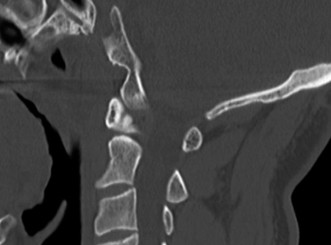

Upon his return five years later, the imaging profile was drastically different. Standing lateral radiographs now revealed a Meyerding Grade 2 spondylolisthesis at L5-S1, indicating that the L5 vertebral body had translated anteriorly by 25% to 50% over the sacral promontory. Furthermore, there was a noticeable collapse of the L5-S1 intervertebral disc space, signifying advanced degenerative changes secondary to the altered biomechanics and chronic instability. We also meticulously measured the patient's spinopelvic parameters on a standing 36-inch scoliosis cassette. His Pelvic Incidence (PI) was measured at 65 degrees (high), which mathematically dictates a higher Sacral Slope (SS) and Pelvic Tilt (PT). A high PI is a known biomechanical risk factor for the progression of spondylolisthesis, as it creates a steeper lumbosacral shear angle, placing immense anterior translational force across the compromised L5-S1 segment.

Focusing on structural and mechanical etiologies, the primary differential diagnosis for this patient's initial presentation centered around the various classifications of spondylolisthesis and discogenic pathology. The Wiltse classification of spondylolisthesis categorizes the condition into dysplastic, isthmic, degenerative, traumatic, and pathologic types. Dysplastic spondylolisthesis involves congenital anomalies of the upper sacrum or the neural arch of L5, often leading to severe slips in early childhood. Degenerative spondylolisthesis, driven by facet joint osteoarthritis and ligamentum flavum hypertrophy, is almost exclusively seen in older adults (typically >50 years old) and most commonly affects the L4-L5 level. Traumatic spondylolisthesis requires a high-energy mechanism resulting in an acute fracture of the neural arch other than the pars. Therefore, the insidious onset of pain in an adolescent athlete with repetitive hyperextension perfectly aligns with the isthmic subtype.

We considered several surgical options. A direct pars repair (such as the Buck, Scott, or Morscher techniques) was immediately ruled out. While pars repairs are excellent motion-preserving options for young patients with isolated pars defects and normal intervertebral discs, they are absolutely contraindicated in the presence of a spondylolisthesis greater than Grade 1 or when there is MRI evidence of disc degeneration. Attempting a pars repair in this patient would fail to address the underlying instability and the degenerated disc, inevitably leading to continued pain and hardware failure. An isolated decompression (Gill laminectomy) without fusion was also rejected. Resecting the loose neural arch removes the compressive fibrocartilaginous tissue but further destabilizes the spine. In an active 20-year-old, an isolated Gill procedure carries an unacceptably high risk of catastrophic postoperative slip progression.